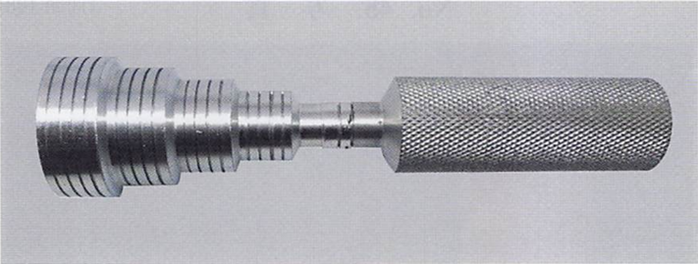

75歳の男性。慢性歯周炎に対する歯周基本治療終了後、3か月間隔で歯周病のメインテナンスと初期の根面う蝕の管理としてフッ化物歯面塗布を行っている。来院時、歯周ポケットの検査を行った後に用いる器材の写真を別に示す。 3番目に用いるのはどれか。1つ選べ。

a. ①

b. ②

c. ③

d. ④

解答を見る

d